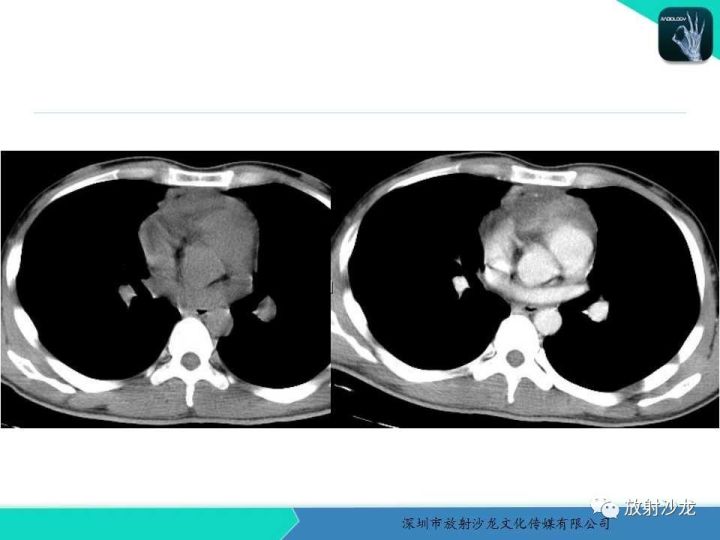

【病例】纵隔卵黄囊瘤1例CT影像表现